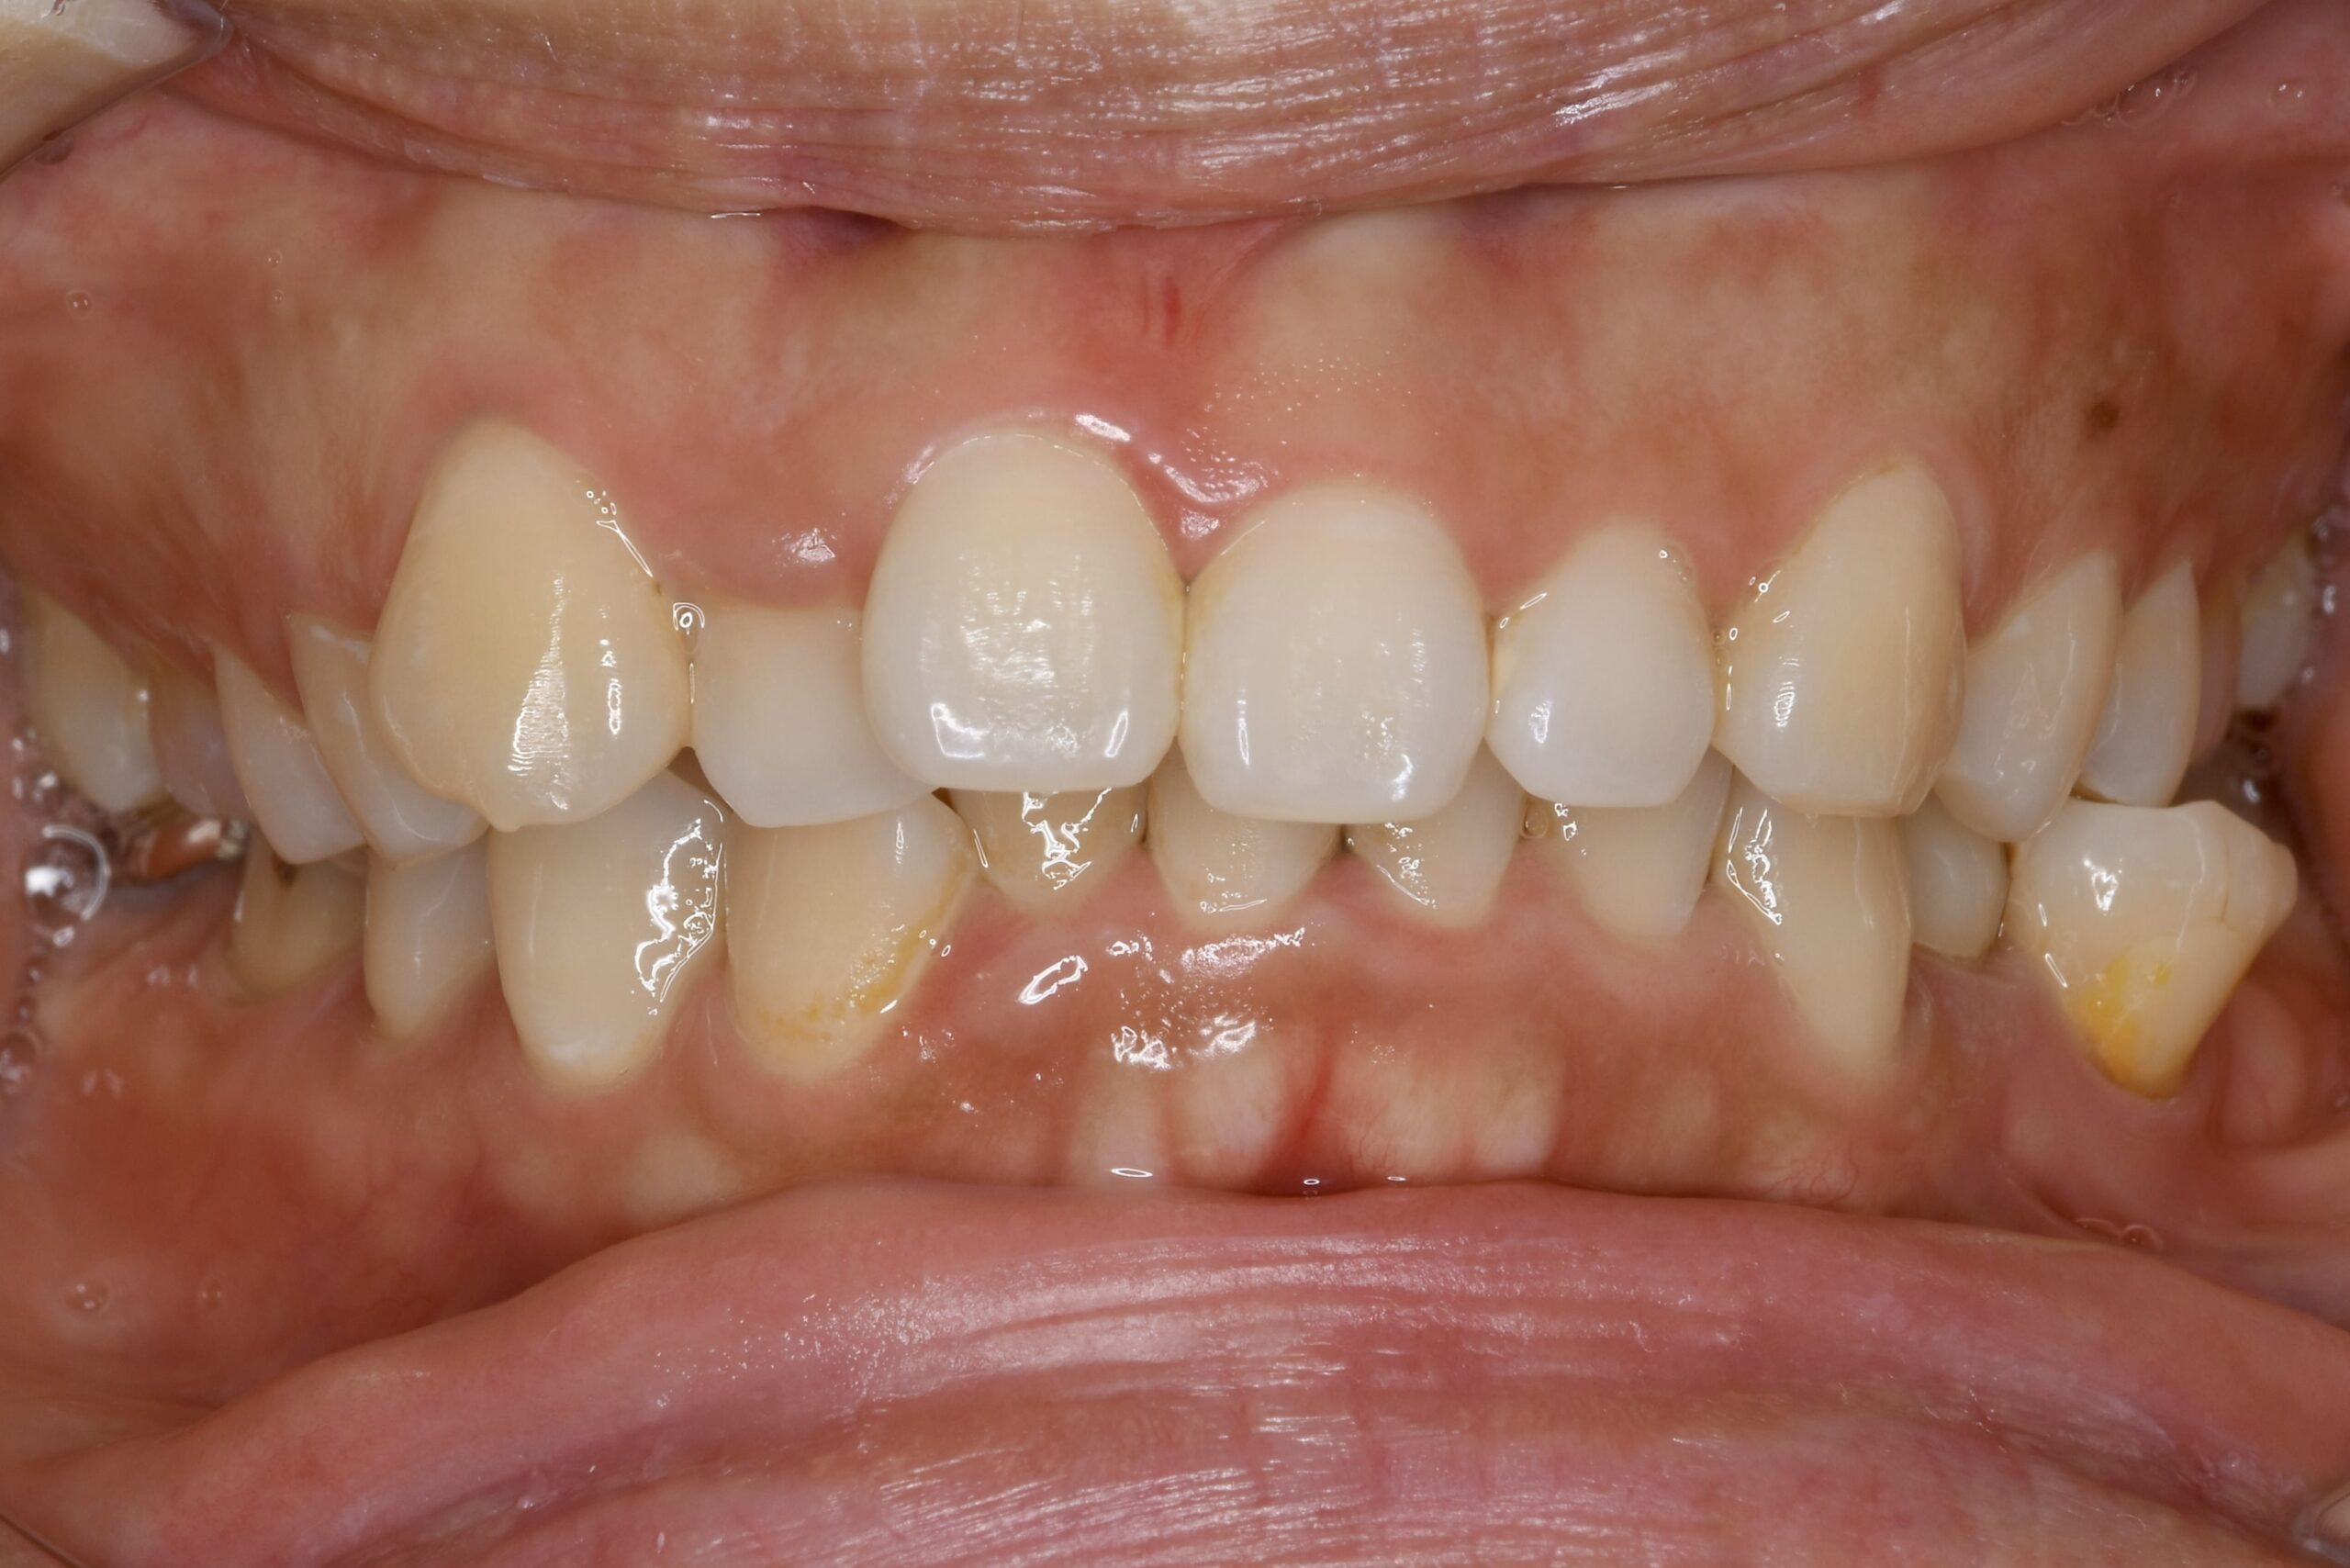

乳歯と永久歯が混在する時期に行う矯正歯科治療です。

顎や口腔機能の成長・発育といった「土台」から正しい歯並びへ導く、お子様ならではの矯正治療が行えます。

負担を考えた、お子様一人ひとりに適切な装置を使用します。